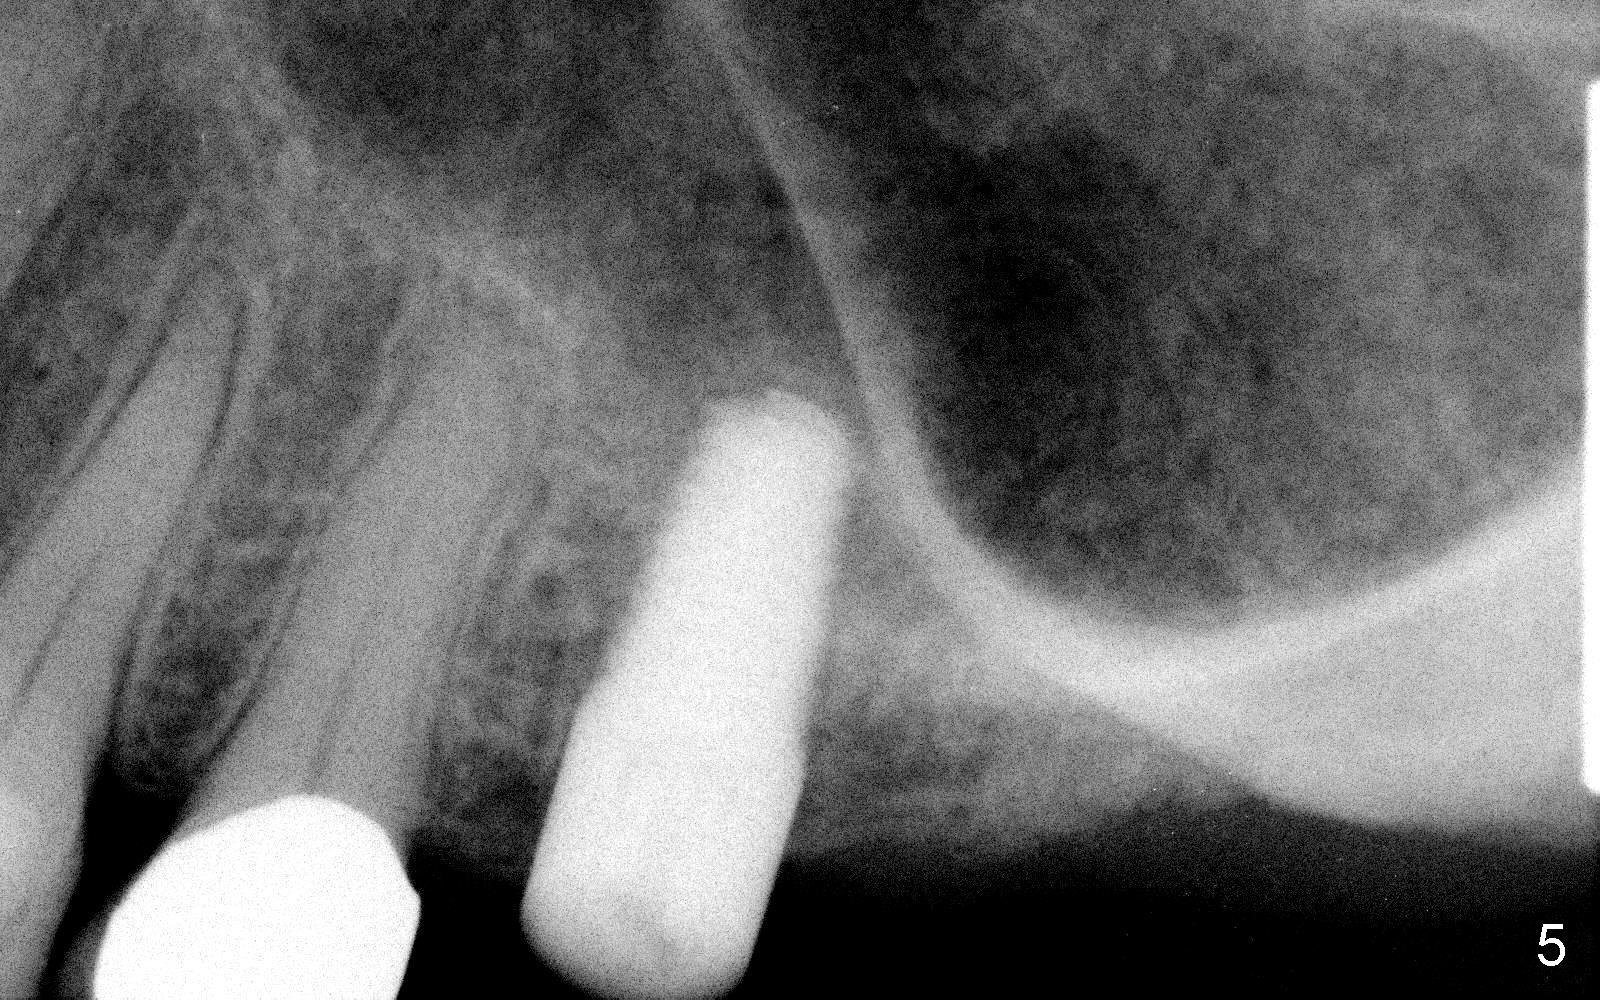

Fig.5, 6 are taken 3 and 4 months post implantation (I: implant; A: abutment).

One year 2 months post cementation, the patient complains of inability to chew on the left. It appears that the crown at the site of #14 (Fig.8) is not as large as the tooth #3 (Fig.7); the occlusal contact of the crown is less than that of the tooth #3. The complaint remains the same after crown being remade. It appears that implant at #15 is needed (Fig.9: 1 year 9 months post cementation of #14 crown). The crestal cortical bone is thicker around the implant 2 years 4 months post cementation (Fig.10).